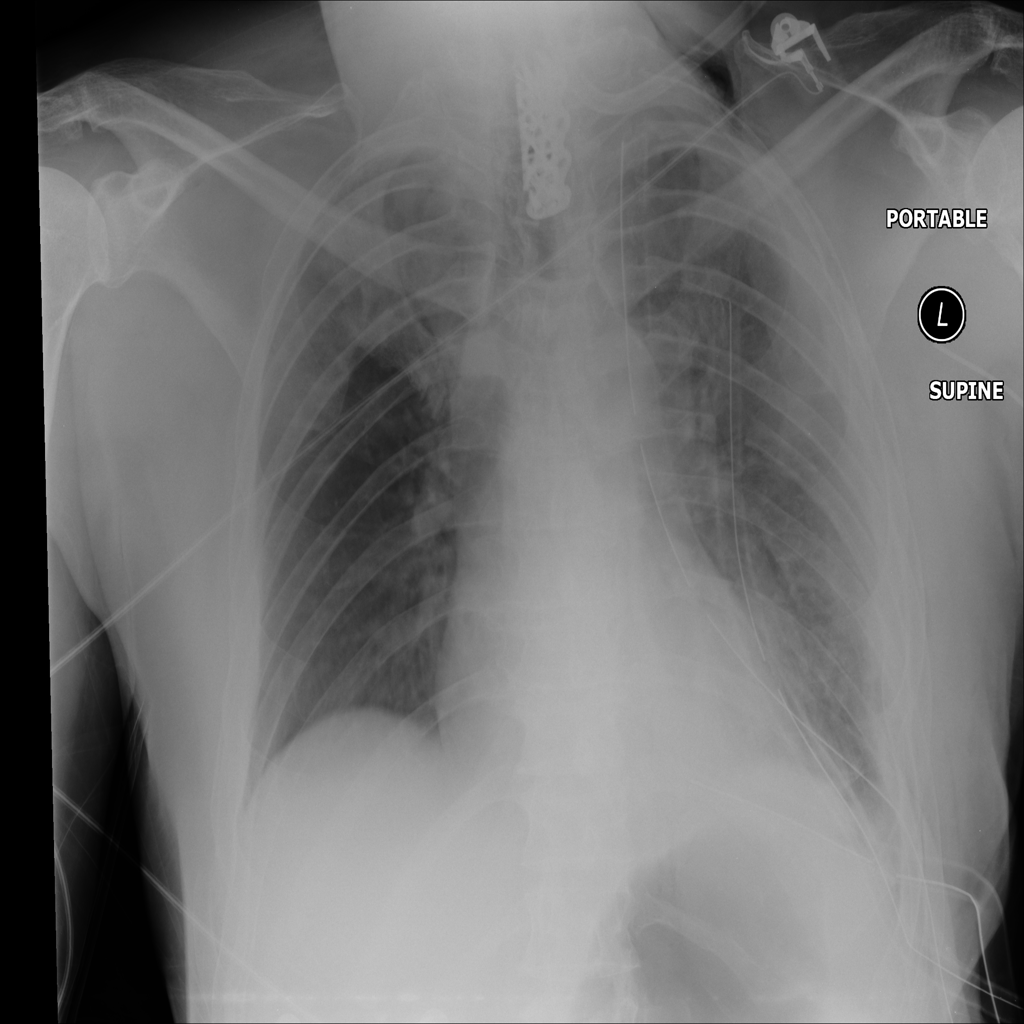

PAT-55FC · IMG-030Emphysema

PAT-55FC · IMG-030

AP